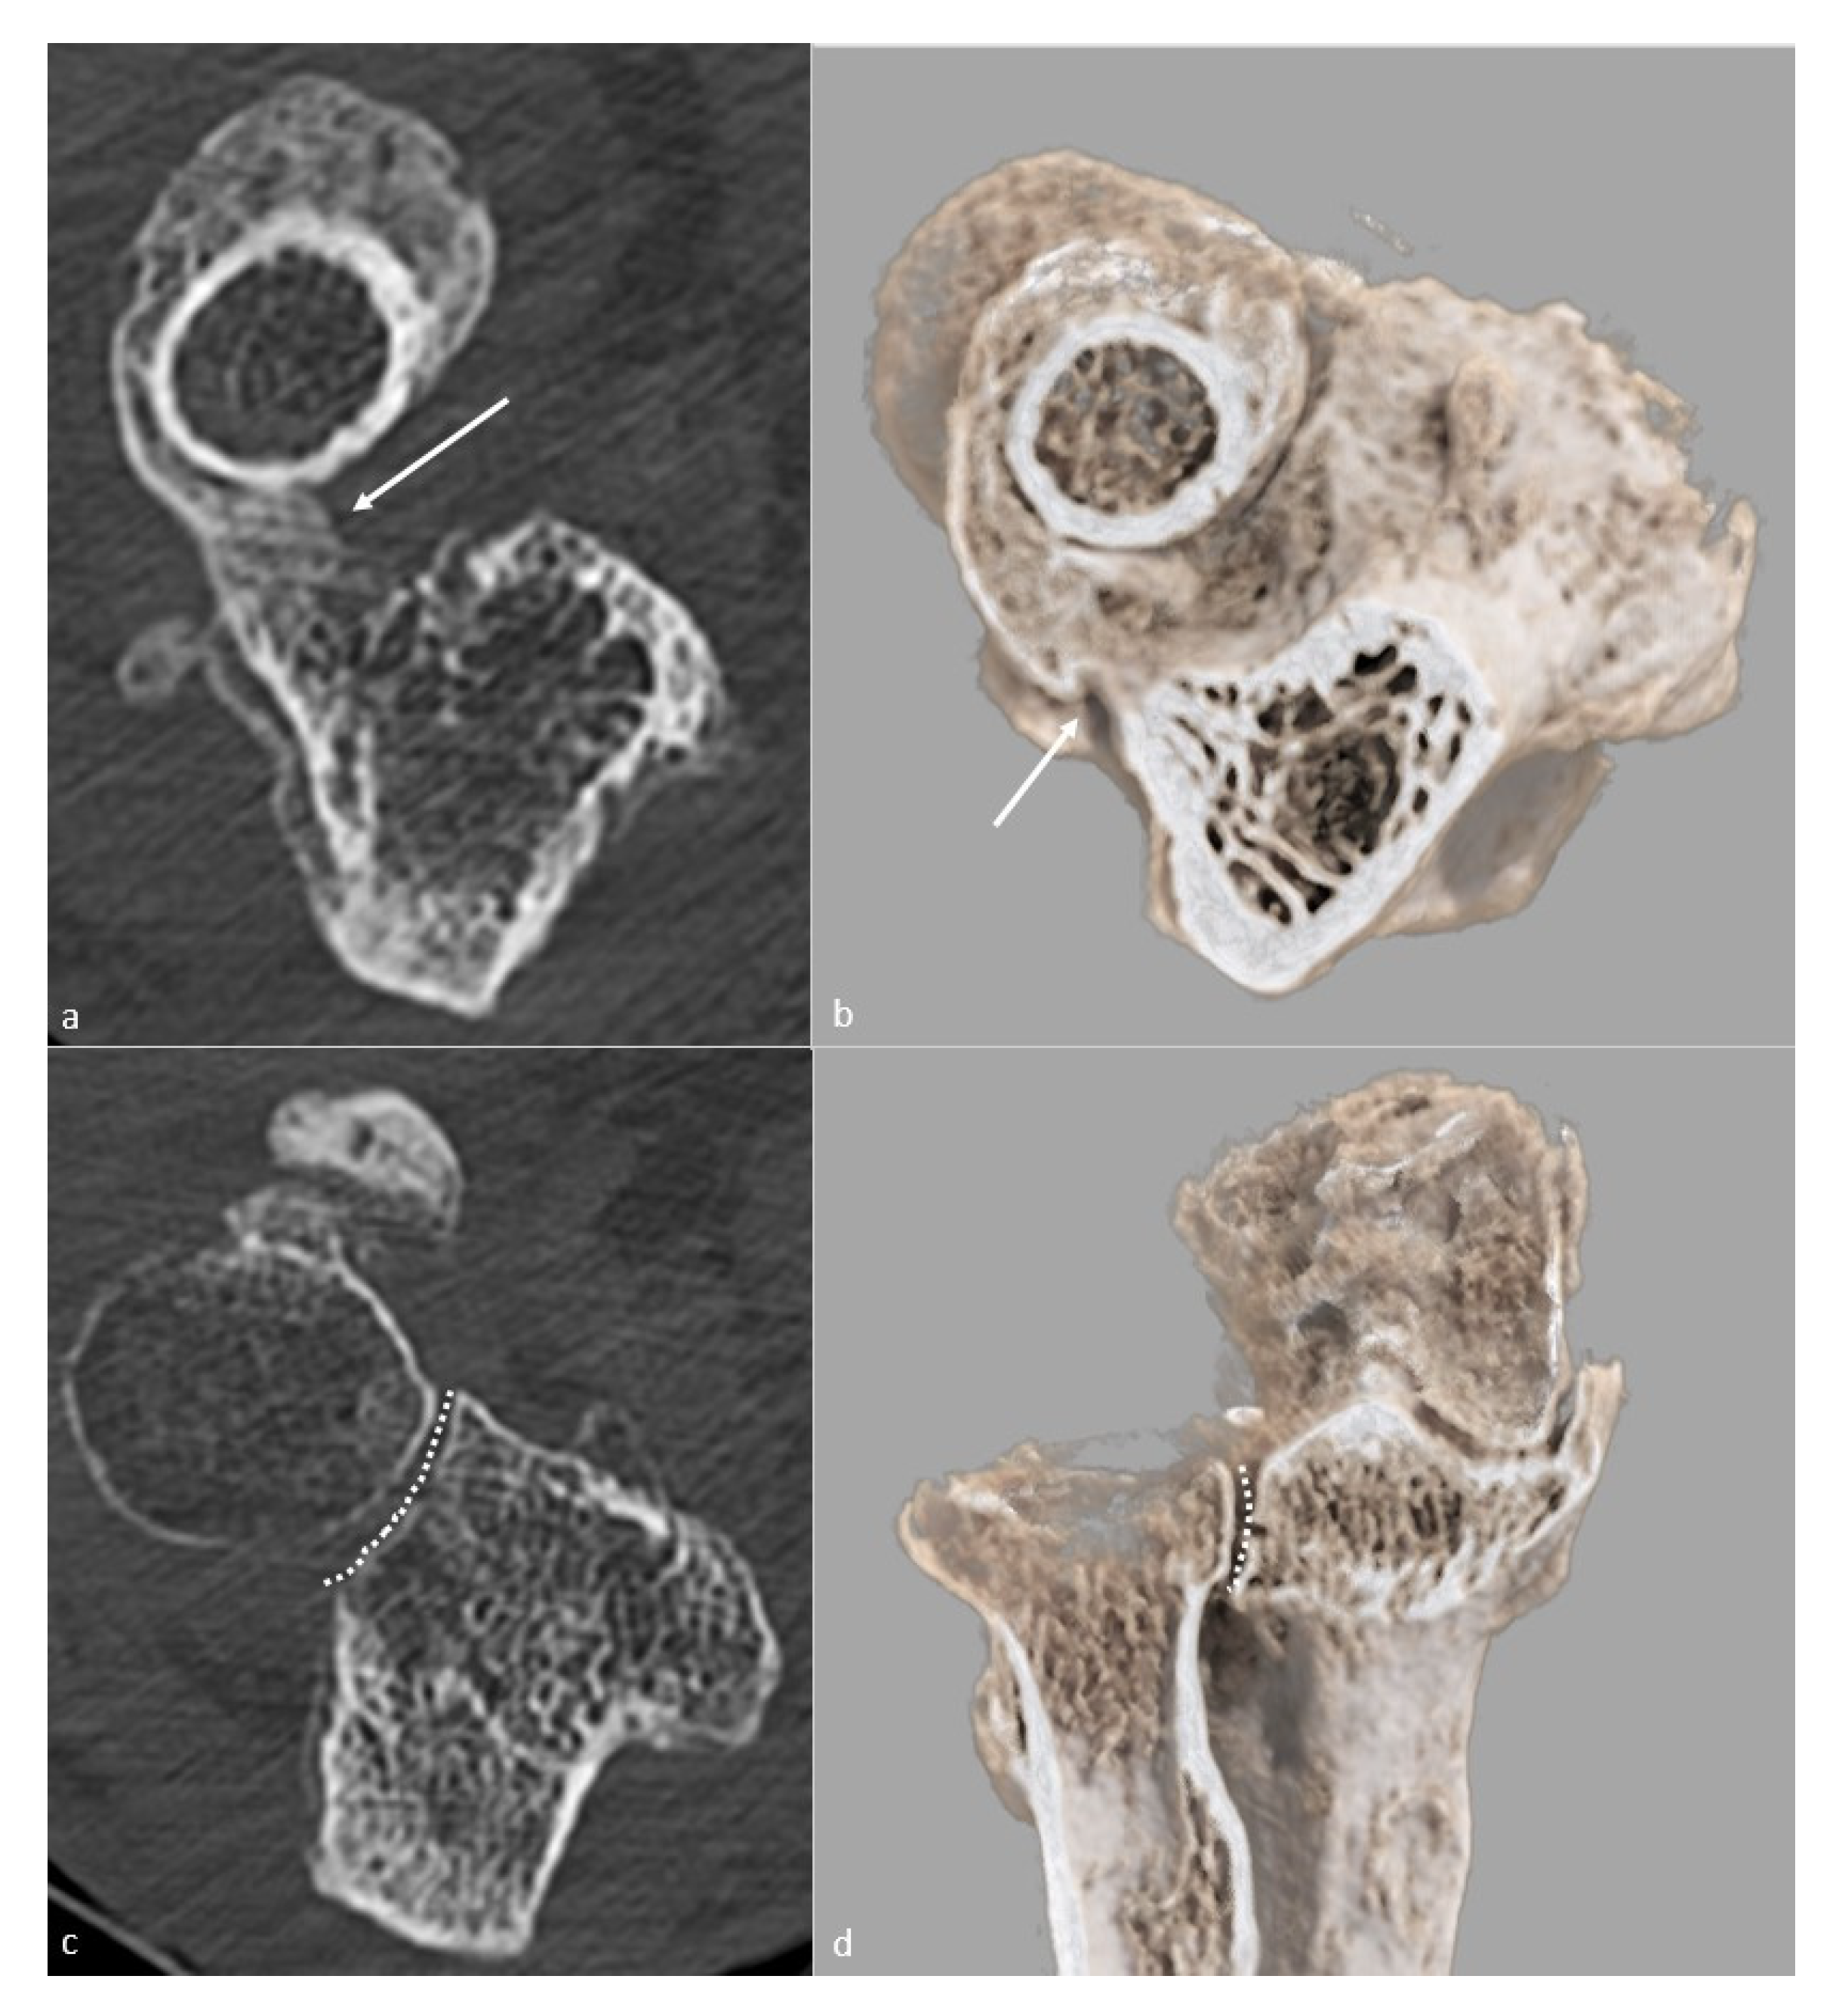

5.3. CT and CT Arthrography

| Forearm rotation dysfunction | CT |

| Proximal radioulnar bony ankylosis | |

| Malunion or nonunion of the radial head | |

| Posttraumatic sequelae of the radial head | |